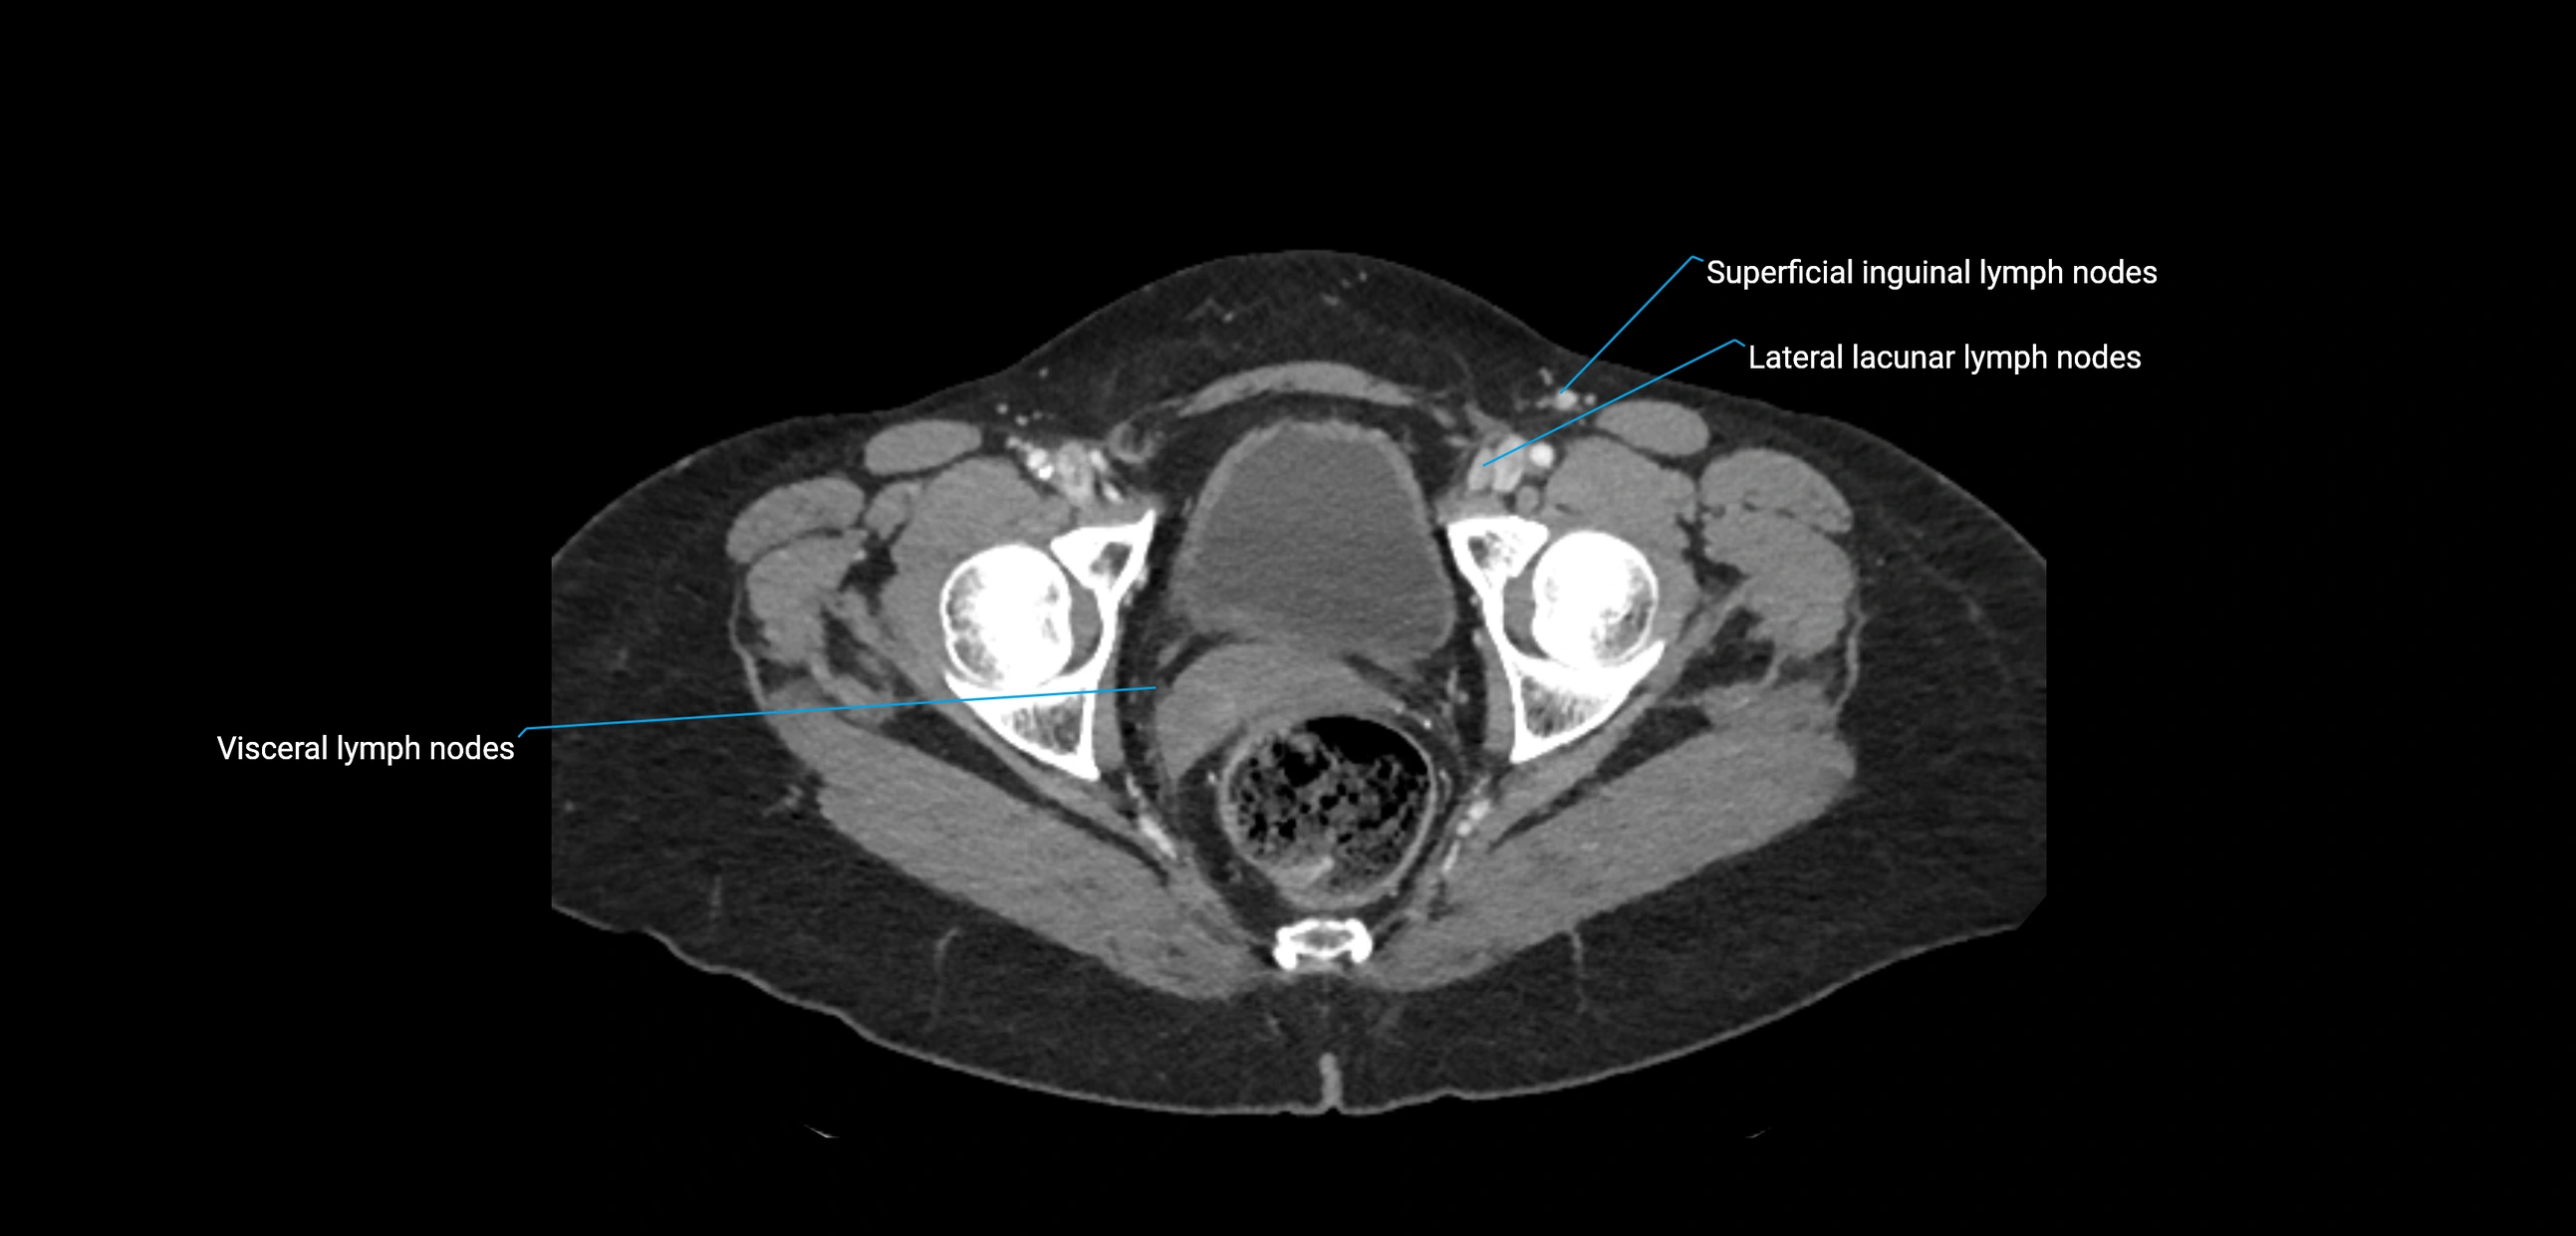

CT Appearance

CT Pre-Contrast:

• Nodes appear as soft-tissue density nodules adjacent to the aorta and IVC

• Calcification may be seen in chronic infections (e.g., tuberculosis)

CT Post-Contrast:

• Normal nodes enhance homogeneously

• Malignant nodes may show heterogeneous enhancement, central necrosis, or conglomerate formation

• Size >1 cm short axis is suspicious, though morphology and distribution are equally important

CT image

image